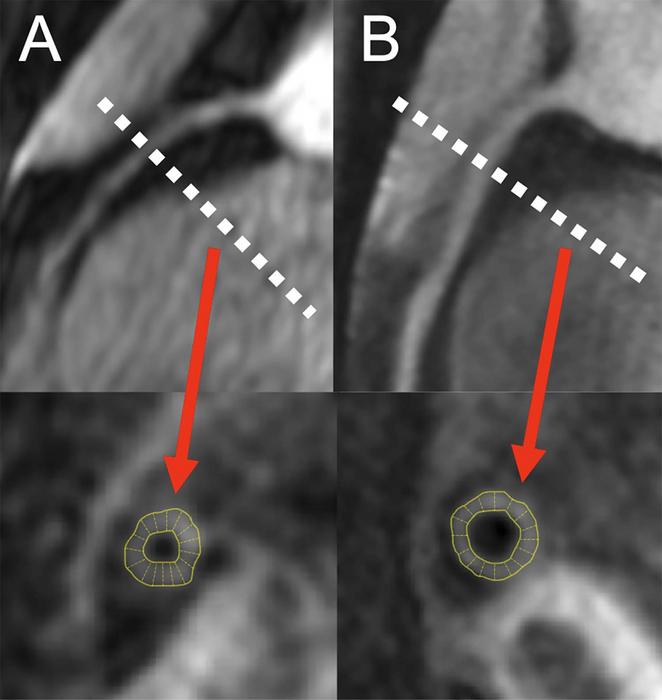

Researchers at the National Institutes of Health (NIH) set out to assess early coronary atherosclerosis burden, and its relation to how the heart is functioning, in people living with HIV who were asymptomatic and had low cardiovascular disease risk. For the study, the researchers recruited 74 adults (mean age of 49 years) living with HIV without known cardiovascular disease and 25 matched healthy controls (mean age of 46 years). Controls were negative for HIV and were required to be healthy with no known significant medical conditions, including coronary disease. All underwent MRI to measure coronary vessel wall thickness and an echocardiogram to assess left ventricular function.

The results showed increased coronary vessel wall thickness in the HIV group, compared to controls. The increased coronary artery vessel wall thickness was independently associated with elevated left ventricular mass index and impaired diastolic function.